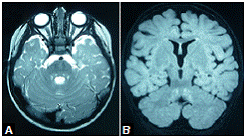

La resonancia magnética (RM) cerebral simple practicada a los 10 meses, mostraba leucoencefalopatía parieto-occipital, e hiperintensidad del tracto tegmental central y de los núcleos delgado y cuneiforme (figura 1). En el electroencefalograma (EEG) se evidenció actividad epileptiforme focal témporo-parietal izquierda. Con los estudios metabólicos se descartó aminoacidopatía, aciduria orgánica, leucodistrofia metacromática y enfermedad del peroxisoma.

A partir de los 18 meses de vida, la niña no volvió a tener convulsiones, pero en la RM cerebral persistía la hiperintensidad del tracto tegmental central, aunque habían desaparecido las lesiones de la sustancia blanca parieto-occipital (figura 2). A los dos años de vida, recibía un solo medicamento anticonvulsivo y presentaba rasgos autistas, en tanto que en el electroencefalograma y la RM cerebral ya no aparecían las anomalías previamente descritas (no se muestran las imágenes).

Este es el primer reporte de caso de una paciente afectada por la mutación del gen PCDH19 asociada con leucoencefalopatía y tractopatía posterior reversible. Mediante las RM cerebrales se evidenció que las lesiones involucionaron progresivamente y, a los 24 meses de vida, las imágenes eran normales.